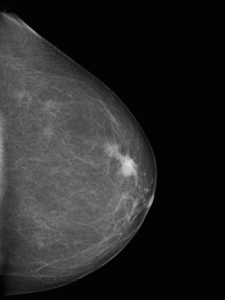

Bei der Mammographie handelt es sich um eine Röntgenaufnahme der Brust.

Die Mammographie ist die derzeit beste Methode, um auffällige Symptome abzuklären.

Seit 2022 haben wir eine neue Möglichkeit Aufnahmen der Brust zu erstellen, die sogenannte Tomosynthese. Die Tomosynthese ist eine spezielle technik zur Ergänzung der digitalen Mammographie. Dabei erstellt das Gerät aus verschiedenen Blickwinkeln von einer Brust 15 oder 25 Einzelbilder, die mittels eines Computers zu einer dreidimensionalen Ansicht zusammengefügt werden. Hierdurch entsteht ein äußerst detailliertes Bild vom Brustgewebe. Durch diese Art der Bilderstellung werden Tumore sichtbar, die möglicherweise durch überlappendes Gewebe verdeckt sind. Zudem können besonders Art und Größer von Läsionen sowie Mikroverkalkungen besser als mit herkömmlichen Methoden analysiert werden.

Die Aufnahmeerstellung erfolgt zumeist im Stehen. Dazu wird die Brust zwischen zwei Plexiglasplatten gedrückt, weil das Röntgenbild besser beurteilt werden kann, wenn das untersuchte Gewebe möglichst dünn ist. Beide Brüste werden aus jeweils zwei Richtungen aufgenommen: von oben nach unten und schräg von der Mitte zur Seite hin. Auch bei Implantaten ist die Mammografie problemlos möglich.